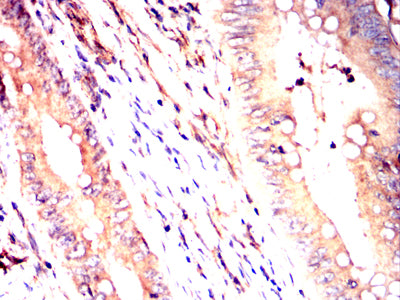

Immunohistochemical analysis of paraffin-embedded human cervical cancer tissues using PDGFA mouse mAb with DAB staining.

Immunohistochemical analysis of paraffin-embedded human rectum cancer tissues using PDGFA mouse mAb with DAB staining.